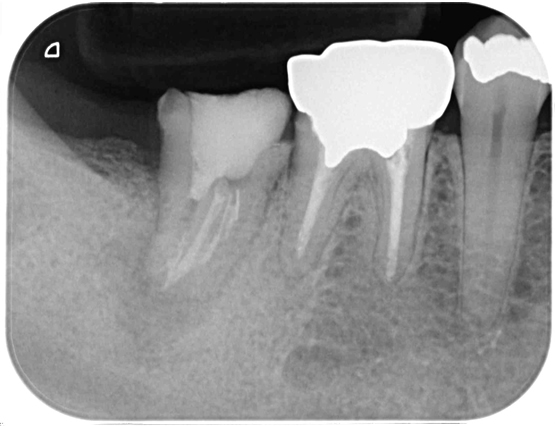

根管治療 症例8

治療中